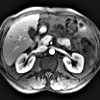

МРТ брюшной полости. Современный метод диагностики, основанный на явлении ядерного магнитного резонанса и применяемый с целью определения патологических изменений во внутренних органах. С помощью процедуры удается визуализировать полые и паренхиматозные структуры: печень, почки, поджелудочную железу, селезенку, пищеварительный канал. В ходе МРТ брюшной полости возможна оценка состояния кровеносных и лимфатических сосудов, расположенных в данной анатомической зоне. Исследование позволяет диагностировать дегенеративные, воспалительные и опухолевые процессы, определять перемещение физиологических жидкостей, выявлять травматические повреждения. МРТ брюшной полости является неинвазивным методом диагностики, может осуществляться нативно или с использованием контраста.

Магнитно-резонансная томография брюшной полости использовалась в медицине в течение относительно короткого времени - с 1980-х годов, за это время, метод был признан одним из наиболее информативных и безопасных для здоровья пациента. В исследовании используются электромагнитные волны определенной частоты, которые взаимодействуют с атомами водорода, расположенными в клетках человеческого организма. Во время магнитно-резонансной томографии брюшной полости специалист получает несколько изображений исследуемого органа в разных проекциях и плоскостях. Это позволяет построить трехмерную модель исследуемой области, определить характеристики анатомического строения органов, оценить размеры, структуру и другие характеристики патологических очагов, диагностировать заболевания даже на ранних стадиях развития, еще до симптомы.

Безопасность техники позволяет сканировать даже детям и беременным женщинам (начиная со второго триместра). МРТ брюшной полости имеет клиническое значение для таких областей практической медицины, как гастроэнтерология, абдоминальная хирургия, сосудистая хирургия, ангиология. МРТ брюшной полости также довольно популярна в онкологии, поскольку показывает точное местоположение опухоли, ее размер и степень распространения в различных анатомических структурах. Использование контрастного вещества позволяет четко визуализировать сосуды, выявить участки нарушения кровотока и лимфотока, воспалительные изменения.